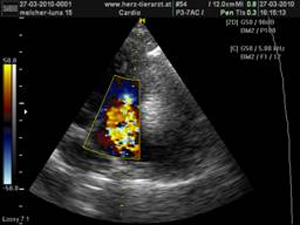

In der Tiermedizin wird der gleiche Ultraschall verwendet wie bei der Untersuchung der ungeborenen Babys beim Menschen . So ist es z.B. möglich Leber, Milz und Prostata zu prüfen, Harnblasensteine zu entdecken oder eben einen Blick auf die ungeborenen Katzen- oder Hunde- Babys zu werfen. Mit dem Farbdoppler- und Spektraldoppler- Ultraschall kann man schließlich noch Blutgefäße und Herzfunktion überprüfen.

Mehr Infos auf: www.herz-tierarzt.at